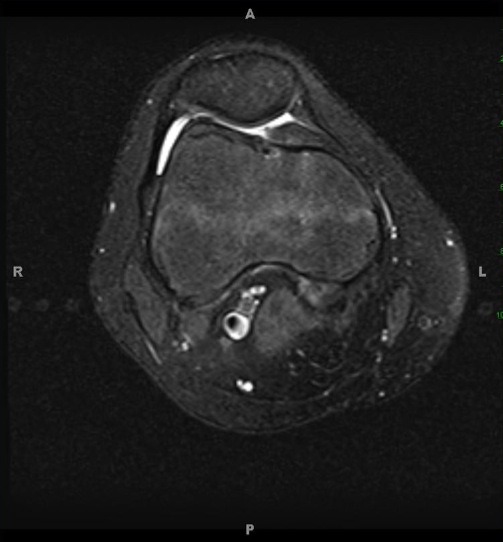

Figure 3 for case Mild alta and early mucoid ACL

Figure 3